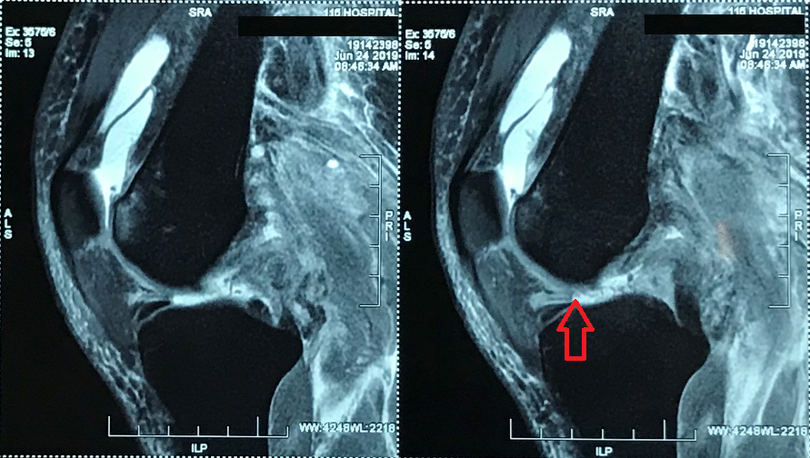

Tại Khoa Điều trị theo yêu cầu – Y học thể thao của Bệnh viện, kết quả chụp MRI khớp gối trái cho thấy, bệnh nhân đứt hoàn toàn đoạn gần dây chằng chéo trước, đứt hoàn toàn đoạn gần dây chằng chéo sau, đứt hoàn toàn đoạn gần dây chằng bên bên ngoài và bong gân độ I dây chằng bên bên trong.

![]() |

| Hình ảnh bị đứt nhiều dây chằng khớp gối trái của bệnh nhân trước khi mổ |